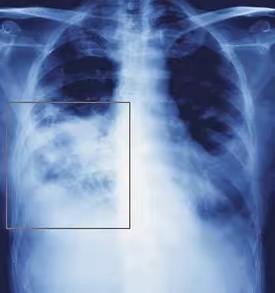

后来患者被诊断为右肺肺炎,如上图方框内便是炎症部分。虽然导致患者持续咳嗽的原因找到了,但是家长却拒绝了医生关于住院治疗的建议。